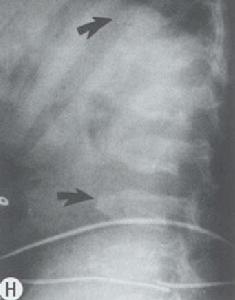

(三)外胚層組織營養變性及異常鈣化症群如甲狀旁腺功能減退為時過久,常發現皮膚粗糙,色素沉著、毛髮脫落,指(趾)甲脆軟萎縮,甚而脫落;眼內晶狀體可發生白內障。病起於兒童期者,牙齒鈣化不全,齒釉發育障礙,呈黃點、橫紋、小孔等病變。患兒智力多衰退、腦電圖常有異常表現,可出現癲癇樣波(不同於原因不明性癲癇,於補鈣後,癲癇樣波可消失):頭顱X線片可見基底節鈣化,骨質也較正常緻密,有時小腦亦可鈣化。